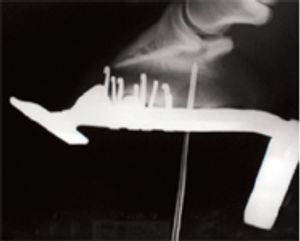

Solving the mathematical needs of a Grade IV laminitic foot.

How to meet the mathematical needs of the higher grades of laminitis.

The mathematical needs of lower grades of laminitis.